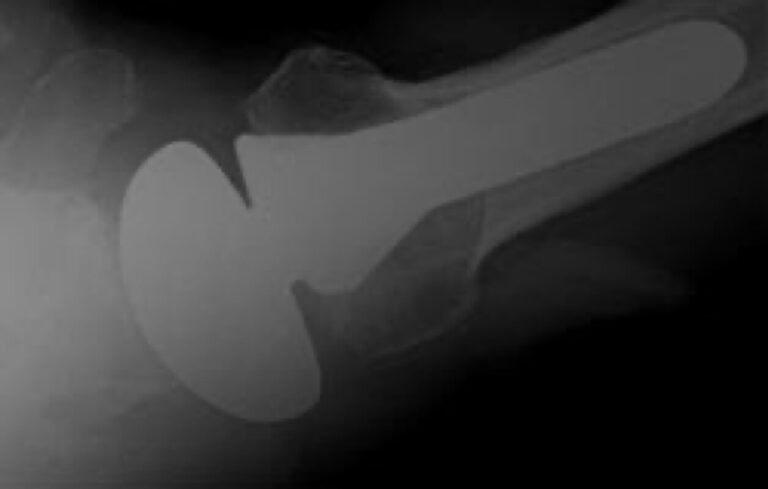

Stryker/Wright/Tornier, Solar Bipolar